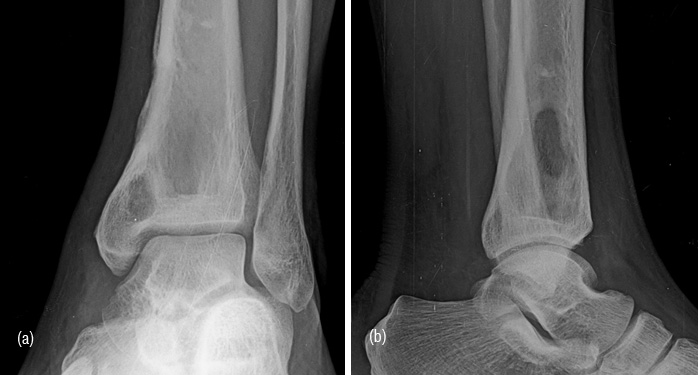

Inspite of introduction of several antibiotics, osteomyelitis, specially of long bones is still encountered. Brodie’s abscess a form of subacute bacterial osteomyelitis may resemble a neoplasm. Radiological characterists include an oval or elongated lucent lesion in the metaphysis with sclerotic border. A small sequestrum may be occasionally noted along with minimal periosteal reaction (Figure 12a,b,c).

Figure 12: (a, b) Brodie’s abcess in the lower end of tibia with minimal sclerosis along the border, (c) Brodie’s abscess along with periosteal reaction in the lower end of tibia.

Tuberculosis (TB) of the bones is less common than joint tubeculosis. Cystic type of tuberculosis may be confused for a bone tumor. Radioloigcal characteristics are almost the same as Brodie’s abscess. However, reactive new bone and periosteal reaction is minimal (Figure 13ab). Clinical and laboratory details will establish the diagnosis.

Figure 13a,b: TB abscess of lower end of tibia.